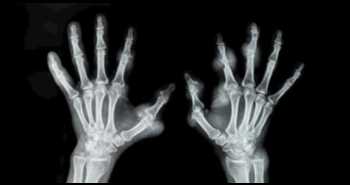

Терапия фторидом диамина серебра (ФДС) может быть эффективным методом лечения поражений поверхности корня зуба у ослабленных пациентов пожилого возраста.

Результаты исследования, опубликованные в Journal of Dentistry, свидетельствуют, что регулярное использование 38 % раствора фторида диамина серебра для местного применения каждые 6 месяцев у лиц пожилого возраста способно обеспечить эффективное предупреждение поражений поверхности корня зуба и области вокруг коронки.

Chelsea Mitchell и соавт. выполнили исследование серии случаев для оценки остановки развития поражений кариесом поверхности корня зуба у 62 взрослых пациентов (в возрасте ≥ 55 лет) при использовании 38 % раствора ФДС для местного применения. Критерием включения было наличие не менее одного активного поражения корня зуба кариесом. Поражения промывали, сушили воздухом, изолировали и наносили 38 % раствор ФДС при помощи микрощеточки на 2 минуты. Повторную оценку обработанных поражений проводили через 2–3 недели после обработки. Через 6 месяцев лечение проводили снова. Вероятность остановки распространения кариеса зубов оценивали отдельно для поверхности корня зуба и области по краям коронки.

На визит последующего наблюдения пришли 55 пациентов (44 % женщин, средний возраст — 79,8 года). Вероятность купирования поражений при лечении варьировалась от 82,9 до 91,6 %. Через 18 месяцев показатели этого параметра для поверхности корня зуба (91,6 %) были выше по сравнению с областью по краям коронки зуба (89,8 %). У 7 пациентов все поражения разветвленных корней (100 %) были купированы через 6 месяцев.